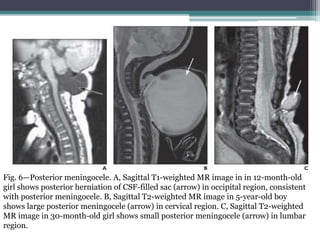

Fig. 6—Posterior meningocele. A, Sagittal T1-weighted MR image in in 12-month-old

girl shows posterior herniation of CSF-filled sac (arrow) in occipital region, consistent

with posterior meningocele. B, Sagittal T2-weighted MR image in 5-year-old boy

shows large posterior meningocele (arrow) in cervical region. C, Sagittal T2-weighted

MR image in 30-month-old girl shows small posterior meningocele (arrow) in lumbar

region.